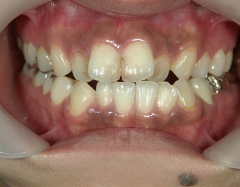

矯正歯科 治療後矯正歯科 全顎ワイヤー矯正 治療後矯正歯科(全顎ワイヤー矯正)治療後

矯正歯科 治療後

no.28_6958_治療後_右.jpgno.28_6958_治療後_正面.jpgno.28_6958_治療後_左.jpg